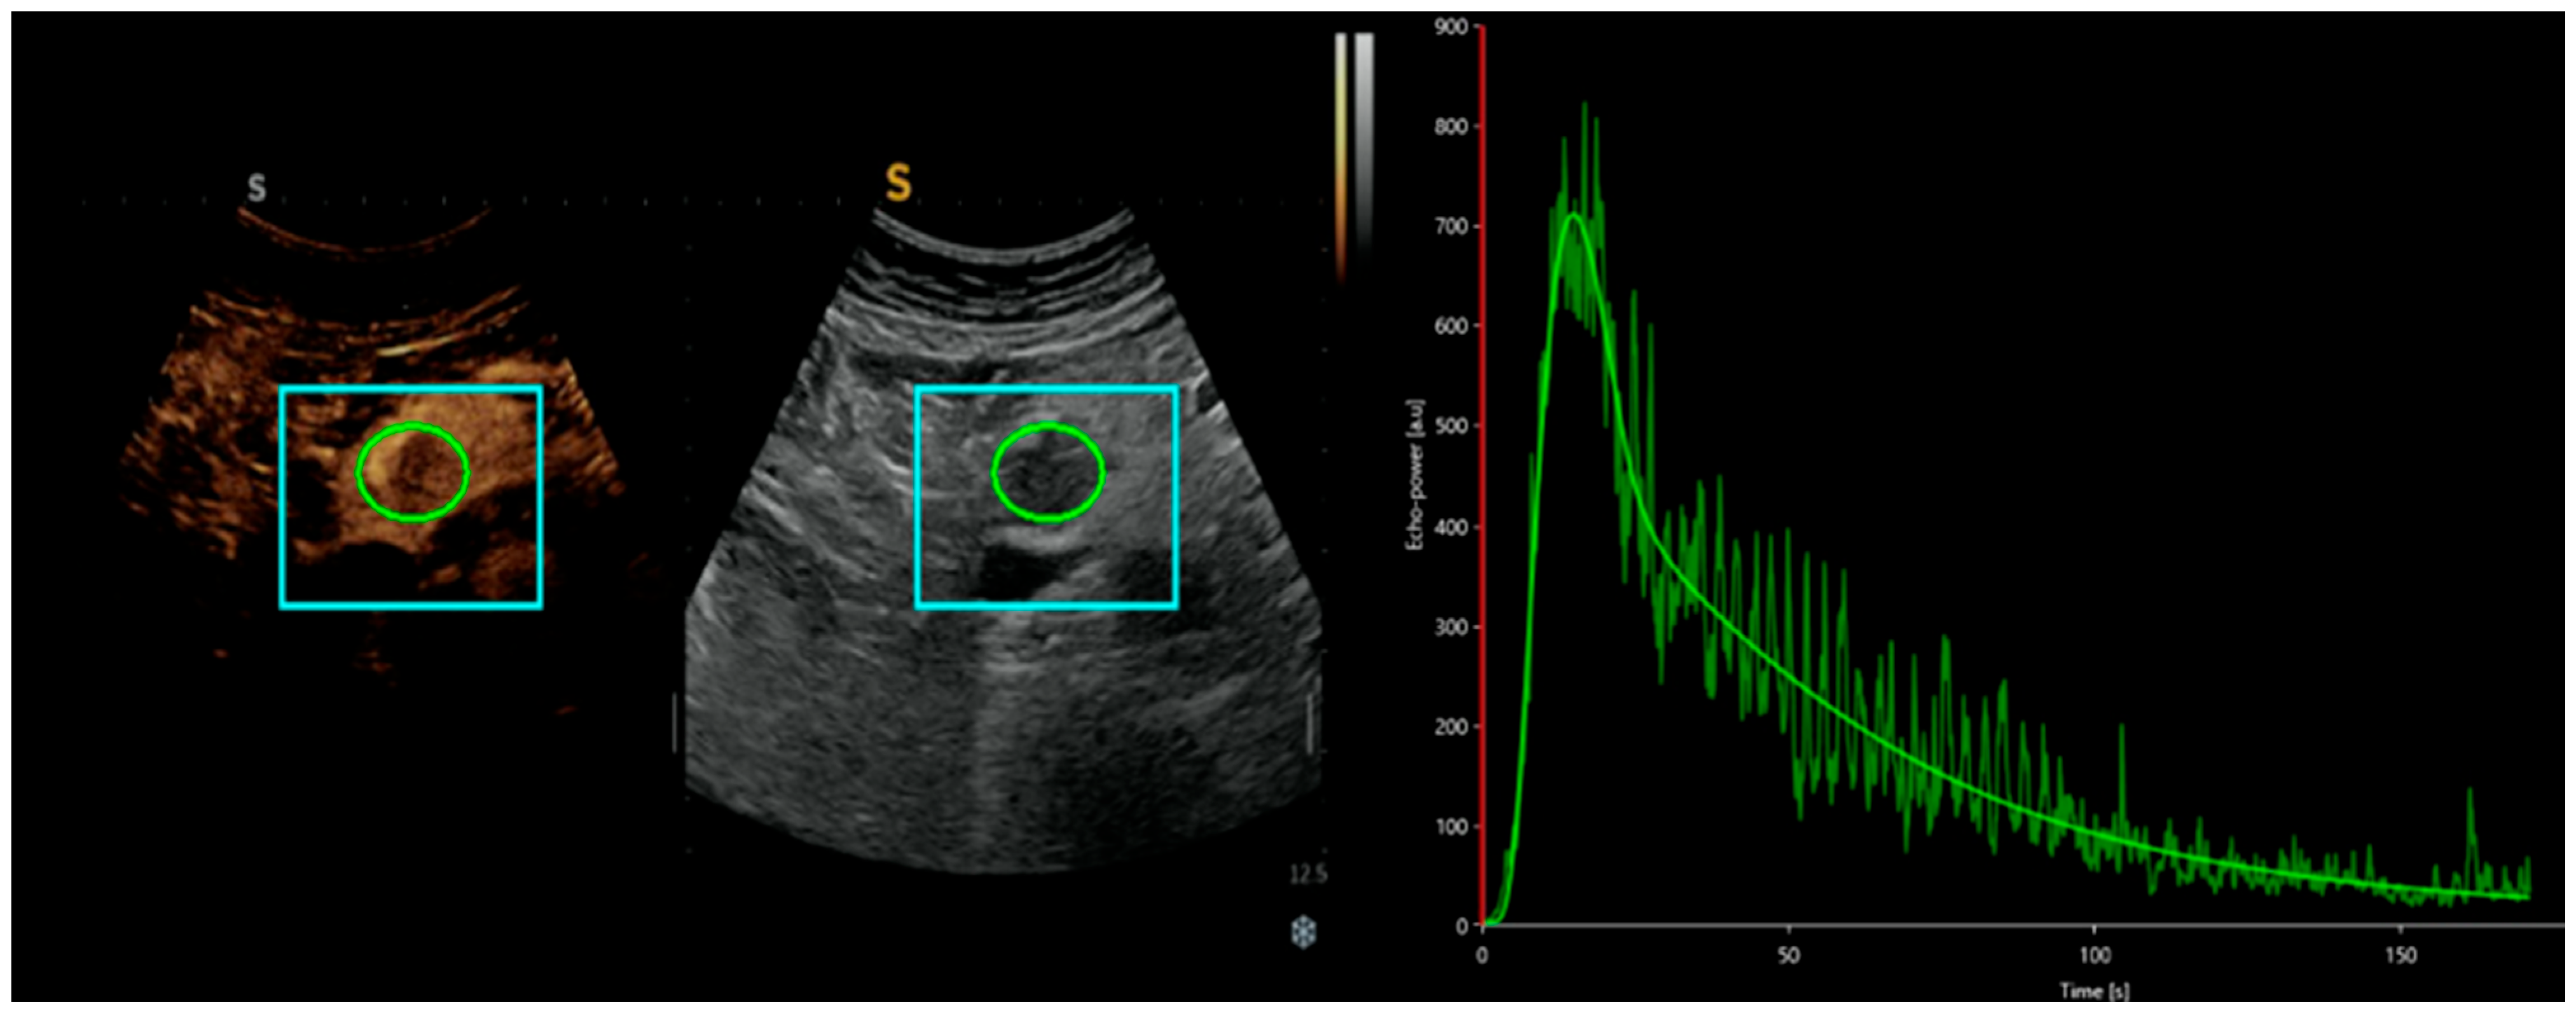

In addition to playing a role in qualitative differential diagnosis, CEUS also enables a dynamic quantitative analysis of the US clip. Using Vuebox software, intensity-time curves (TICs) can be obtained, providing numerical, quantitative, and objective data on the contrast agent behavior in a specific lesion [Figure 1].

Representation of an analysis of a CEUS clip of a pancreatic lesion with Vuebox software, from which a time-intensity curve is obtained, providing numerical values such as peak enhancement, area under the curve, and mean contrast agent transit time.

In this context, the group led by Yang DH et al. demonstrated the use of D-CEUS in analyzing the relationship between the US clip and the grading of NETs. In their population of 42 patients undergoing surgery, they observed that the majority of G1/G2 pNETs showed higher TICs than pancreatic parenchyma, whereas G3/pNECs had lower TICs. By converting these data into quantitative values, they found that CEUS parameters, such as peak enhancement (PE), area under the curve (AUC), and mean transit time (mTT), were significantly higher in G1/G2 pNETs compared to G3/pNECs, with PE and AUC offering high sensitivity and accuracy for predicting G3/pNECs [31].